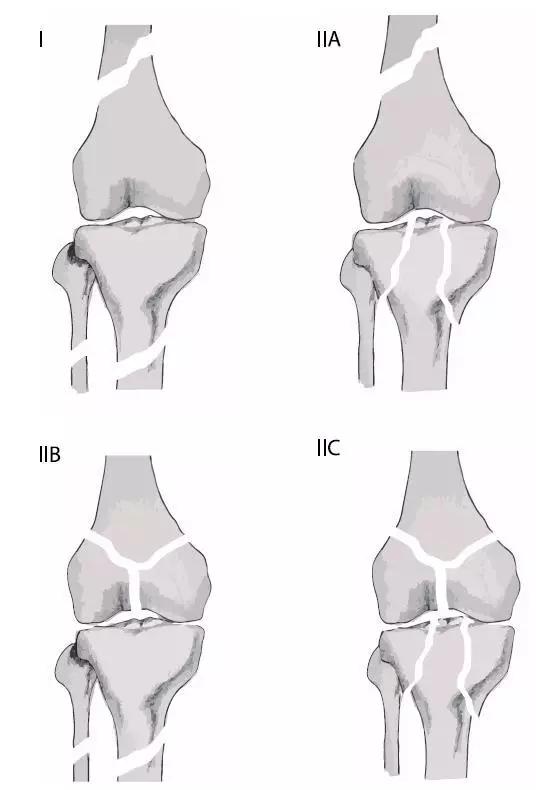

7. 浮膝

特指股骨、胫腓骨同时骨折,膝关节上下无附着而得名。其它浮髋、浮肩与此同理。

浮膝的 Fraser's 分型(来源:Management of the Floating Knee in Polytrauma Patients. Open Orthop J. 2015 Jul 31;9:347-55.)